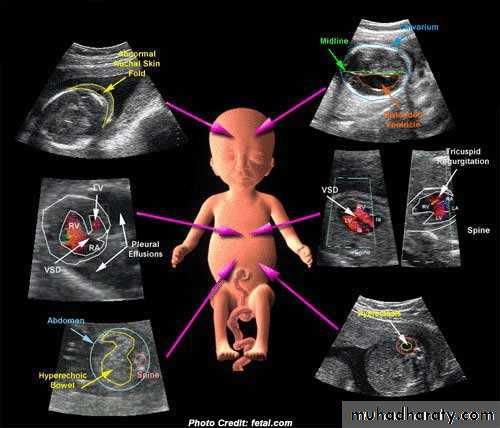

Ultrasound and invasive procedures

Ultrasound is used to guide invasive diagnosticprocedures such as amniocentesis, chorion villus

sampling and cordocentesis, and therapeutic

procedures such as the insertion of fetal bladder

shunts or chest drains.

If fetoscopy is performed, the endoscope is inserted under ultrasound guidance.

This use of ultrasound has greatly reduced the possibility of fetal trauma, as the needle or scope is visualized throughout the procedure and guided with precision to the appropriate place.